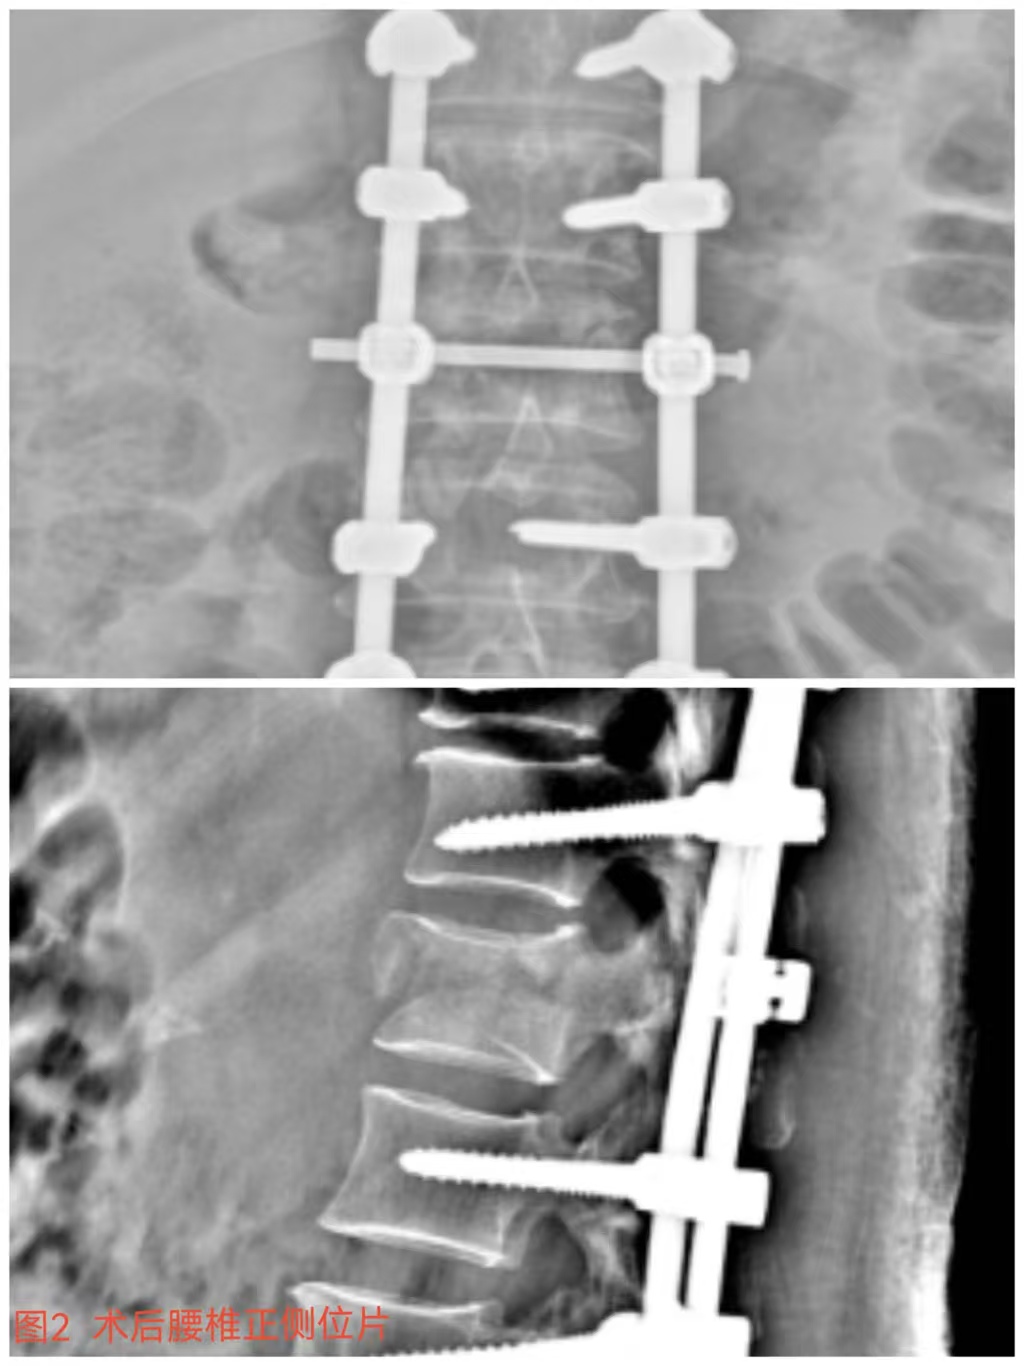

俞德亮副主任醫(yī)師深知病情的嚴(yán)重性,拖得時間越久,脊髓神經(jīng)損傷癥狀越難以恢復(fù),必須把握住早期減壓手術(shù)的關(guān)鍵時間窗,緊急帶領(lǐng)創(chuàng)傷骨科醫(yī)師團隊對該病情進行討論、制定手術(shù)方案,并成功為患者急診行“L1椎體爆裂性骨折伴截癱切開椎板切除+椎管探查減壓+骨折復(fù)位釘棒系統(tǒng)內(nèi)固定術(shù)(圖2)”,該手術(shù)精確解除對脊髓神經(jīng)的壓迫,并通過椎弓根螺釘內(nèi)固定系統(tǒng)對受損的腰椎提供穩(wěn)固的支撐,為后期的康復(fù)創(chuàng)造了良好的條件。